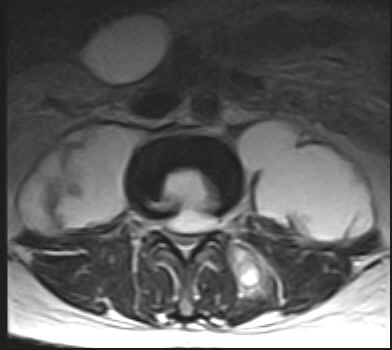

The L1, L2 and L3 vertebral bodies show hypointense areas on the T1W images and these turn hyperintense on the T2W images. The L1-L2 and L2-L3 intervertebral discs are also involved. There is an anterior epidural lesion at the L2 and L3 vertebral levels. It is hypointense with a hyperintense rim on the T1W images and hyperintense with a hypointense rim on the T2W images. This would be suggestive of an abscess. Slight prevertebral soft tissue extension is noted. The psoas muscles are bulky bilaterally and show presence of abscesses. A similar lesion is noted within the left paraspinal muscles.

·                     Tuberculosis tends to involve the soft tissues commonly with abscess formation. Large paravertebral or psoas abscesses (calcifications may be seen) are commonly involved. These may be out of proportion to the degree of involvement of the vertebra or disc. Abscesses may also be seen in the paraspinal region and epidural space. The abscesses are usually located ventrally in the cervical and lumbar spine and posteriorly in the dorsal spine. The leptomeninges may be involved. Intraosseus abscesses may be seen. The abscesses are invariably seen to have a centre which is isointense to hypointense to normal muscle with a slightly hyperintense rim on the T1W images. On the T2W images the centre is hyperintense and the rim hypointense. Contrast enhancement of the rim is noted. These lesions usually yield drainable pus. It may be difficult to distinguish phlegmon (inflammatory mass of granulation tissue) from an abscess. Phlegmon usually shows diffuse contrast enhancement. This inflammatory tissue may tunnel beneath the paraspinous ligaments.